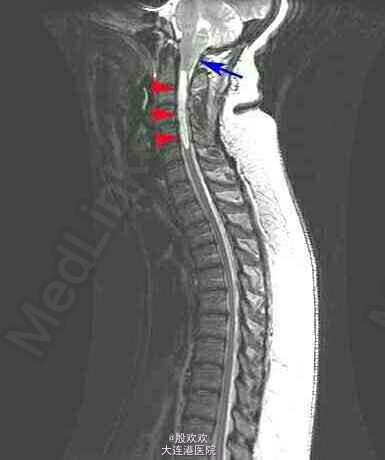

患者,女,51岁,因“右上肢无力萎缩10+年,双上肢麻木5年”入院。患者10+年前感右上肢力弱,逐渐加重,并发现右手肌肉渐萎缩。后双上肢麻木。

查体:生命体征平稳,双上肢皮肤粗糙。专科查体:神清,语利,双侧颈5-胸4水平痛温觉减退。双下肢肌张力稍高,右手骨间肌肉萎缩。双侧腹壁反射消失,双肱二头肌肌腱、肱三头肌肌腱、桡骨膜反射减低,双侧膝反射、踝反射明显增高。 辅助检查:头+颈椎+胸椎MRI:charis畸形并脊髓空洞症。

诊断:脊髓空洞症并小脑扁桃体下疝畸形:charis I型畸形。治疗:给于给于维生素B、ATP、肌苷等营养神经及康复治疗。

脊髓空洞症的病因不明,但是普遍认为,枕大孔区狭窄性病变阻断了脑脊液从脊柱向头部的正常循环,正是因为如此,可以对于charis I型畸形可以行后颅窝减压术,重建脑脊液通路,恢复脑脊液的正常循环状态,虽然少数患者恢复不满意,但大量研究已经证明,其远期疗效肯定。但是临床上,一般先进行内科治疗,如果无效,再和家属沟通性外科手术疗法。